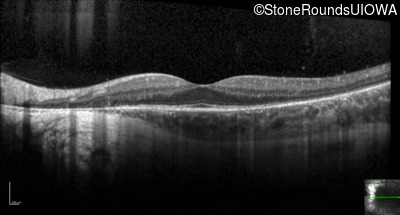

Optical Coherence Tomography - Left - 20/12.5 -2

Exemplar / OCT Stack